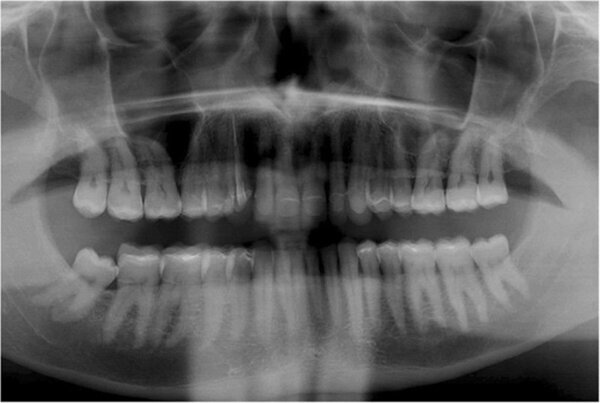

En 2015, un paciente de 47 años se quejó de dolor en la ATM. Teníamos también una solicitud estética, ya que parte de la carilla de uno de los incisivos centrales superiores se había roto (Figs. 1-3). El análisis clínico y radiográfico (Fig. 4) ocasionó una pérdida de altura de la mordida y; una sustancia dental debida a un bruxismo.

Fig. 2. Situación inicial, radiografía panorámica (2015).